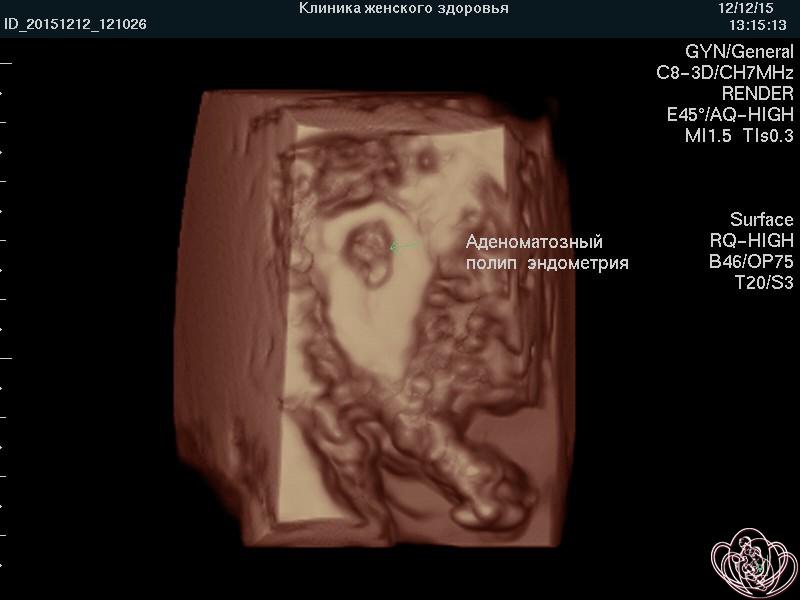

Фото полипов | Курортная клиника женского здоровья

Фото гранулематозного полипа влагалища . Полип влагалища сформировался после некорректного ушивания послеродового разрыва . Фото полипа влагалища после экстирпации матки (полного удаления матки вместе с влагалищной частью шейки матки) .